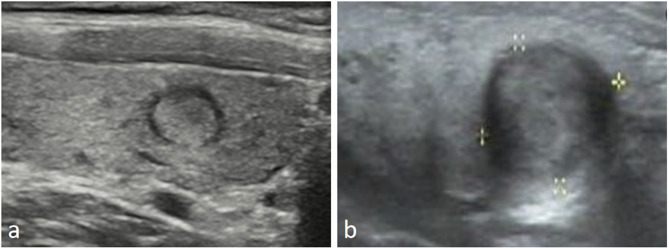

Results: One hundred and sixty patients met the requirements. Benign nodules were mainly characterized by a thin (0.75 ± 0.31 mm) and uniform halo with good integrity, while malignant nodules had a thicker (1.48 ± 0.51 mm) halo with uneven and irregular margins (P < 0.05). The sensitivity and specificity were highest when the cutoff value was 1.09 mm, with 76.08% and 84.29%, respectively. The halos of benign nodules were mostly hyper- or iso-enhanced, whereas the halos of malignant nodules were predominantly hypo-enhanced (P < 0.05). The areas under the curve (AUCs) for CEUS, FNA, and CEUS + FNA were 0.751(95% CI = 0.642-0.841), 0.863(95% CI = 0.767-0.929), and 0.918(95% CI = 0.834-0.967), respectively. Cervical lymph node metastasis occurred in only 13 (11.5%) malignant nodes with halos. The primary pathological components of the halo around malignant nodules were almost reactive hyperplastic fibrous tissue.

Conclusion: The halo surrounding malignant thyroid nodules is thicker, with uneven and irregular margins, and shows hypo-enhancement on CEUS. Combining CEUS with FNA improves the diagnostic efficacy of thyroid nodules with halos. The reactive hyperplastic fibrous halo may be one of the reasons why malignant nodules are less likely to metastasize.